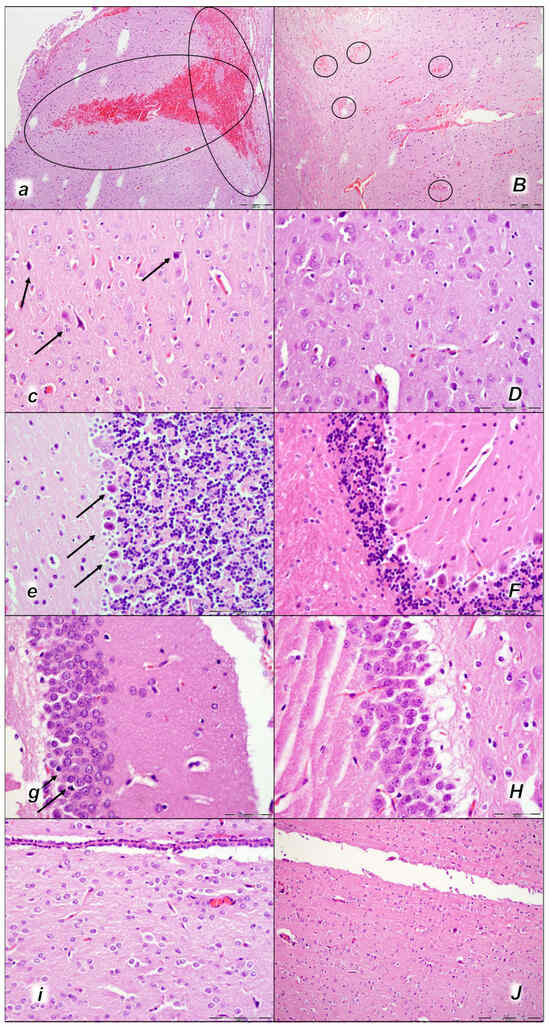

Figure 11.

Brain neuropathological changes, 15 min following laurate application into the inferior caval vein, (a–J). In the control rats (small italic letters), a pronounced edema and congestion in the brain tissue were observed. Focal, pronounced, and deep intracerebral hemorrhage involving areas of brain tissue was observed, affecting areas of the neocortex, the corpus callosum, the amygdala, and the striatum in the brain tissue (a) (marked area). Mild neurodegenerative changes of the central nervous system, such as rare karyopyknotic cells affecting cerebral (c) and cerebellar (e) cortex, a karyopyknosis and degeneration of Purkinje cells of the cerebellar cortex, and karyopyknosis of cortical neurons, were observed (black arrows), including in the hypothalamus/thalamus (g) and hippocampus (i). In the BPC 157-treated rats (capital italic letters), mild edema and congestion in the brain tissue. Intracerebral hemorrhage was visible only within superficial layers of the neocortex (marked area) (B). No neurodegenerative changes of the central nervous system were observed in BPC 157 rats: in the cerebrum (D), cerebellum (F), hypothalamus/thalamus (H), and hippocampus (J). (HE staining; magnification 100×; scale bar 200 µm (a,B); magnification 400×; scale bar 100 μm (c–J)).

2.3.2. Brain Damage

All three assessment time periods (15 min (Table 5, Figure 11), 30 min (Table 5, Figure 12), and 60 min (Table 5, Figure 13) following laurate application showed a pronounced edema and congestion in the brain tissue of the control rats). Pronounced and deep intracerebral hemorrhage involves many brain areas, such as the neocortex, the corpus callosum, the amygdala, and the striatum. Intraventricular hemorrhage was not observed.

In contrast, in the BPC 157-treated rats were less affected, presenting with only mild edema and congestion in the brain tissue and intracerebral hemorrhage only in the superficial layers of the neocortex (15 min (Table 5, Figure 11), 30 min (Table 5, Figure 12), and 60 min (Table 5, Figure 13) following laurate application). No intraventricular hemorrhage was found in treated animals.

After the assessment time period of 15 min, control rats presented mild neurodegenerative changes in the central nervous system; rare karyopyknotic cells affecting the cerebral and cerebellar cortex, a karyopyknosis and degeneration of Purkinje cells of the cerebellar cortex, and karyopyknosis of cortical neurons were observed. In contrast, no neurodegenerative changes of the central nervous system were observed in BPC 157-treated rats (Table 5, Figure 11).

Furthermore, brain lesions rapidly progressed, with control rats severely affected; notably, later than 30 min and 60 min in particular. Moderate and severe neurodegenerative changes were widespread, in the cerebral and cerebellar cortex, hypothalamus/thalamus, and hippocampus, affecting all four regions (Table 5, Figure 12 and Figure 13). There was karyopyknosis and degeneration of the Purkinje cells of the cerebellar cortex, and karyopyknosis of the cortical neurons and pyramidal cells of the hippocampus, as well as hypothalamic neurons. BPC 157-treated rats were much less affected, presenting with no or only rare karyopyknotic cells in all four regions, the cerebral and cerebellar cortex, hypothalamus/thalamus, and hippocampus. Thus, in laurate-administered rats, BPC 157 therapy attenuated/counteracted all inferior caval vein embolization-induced brain lesions.